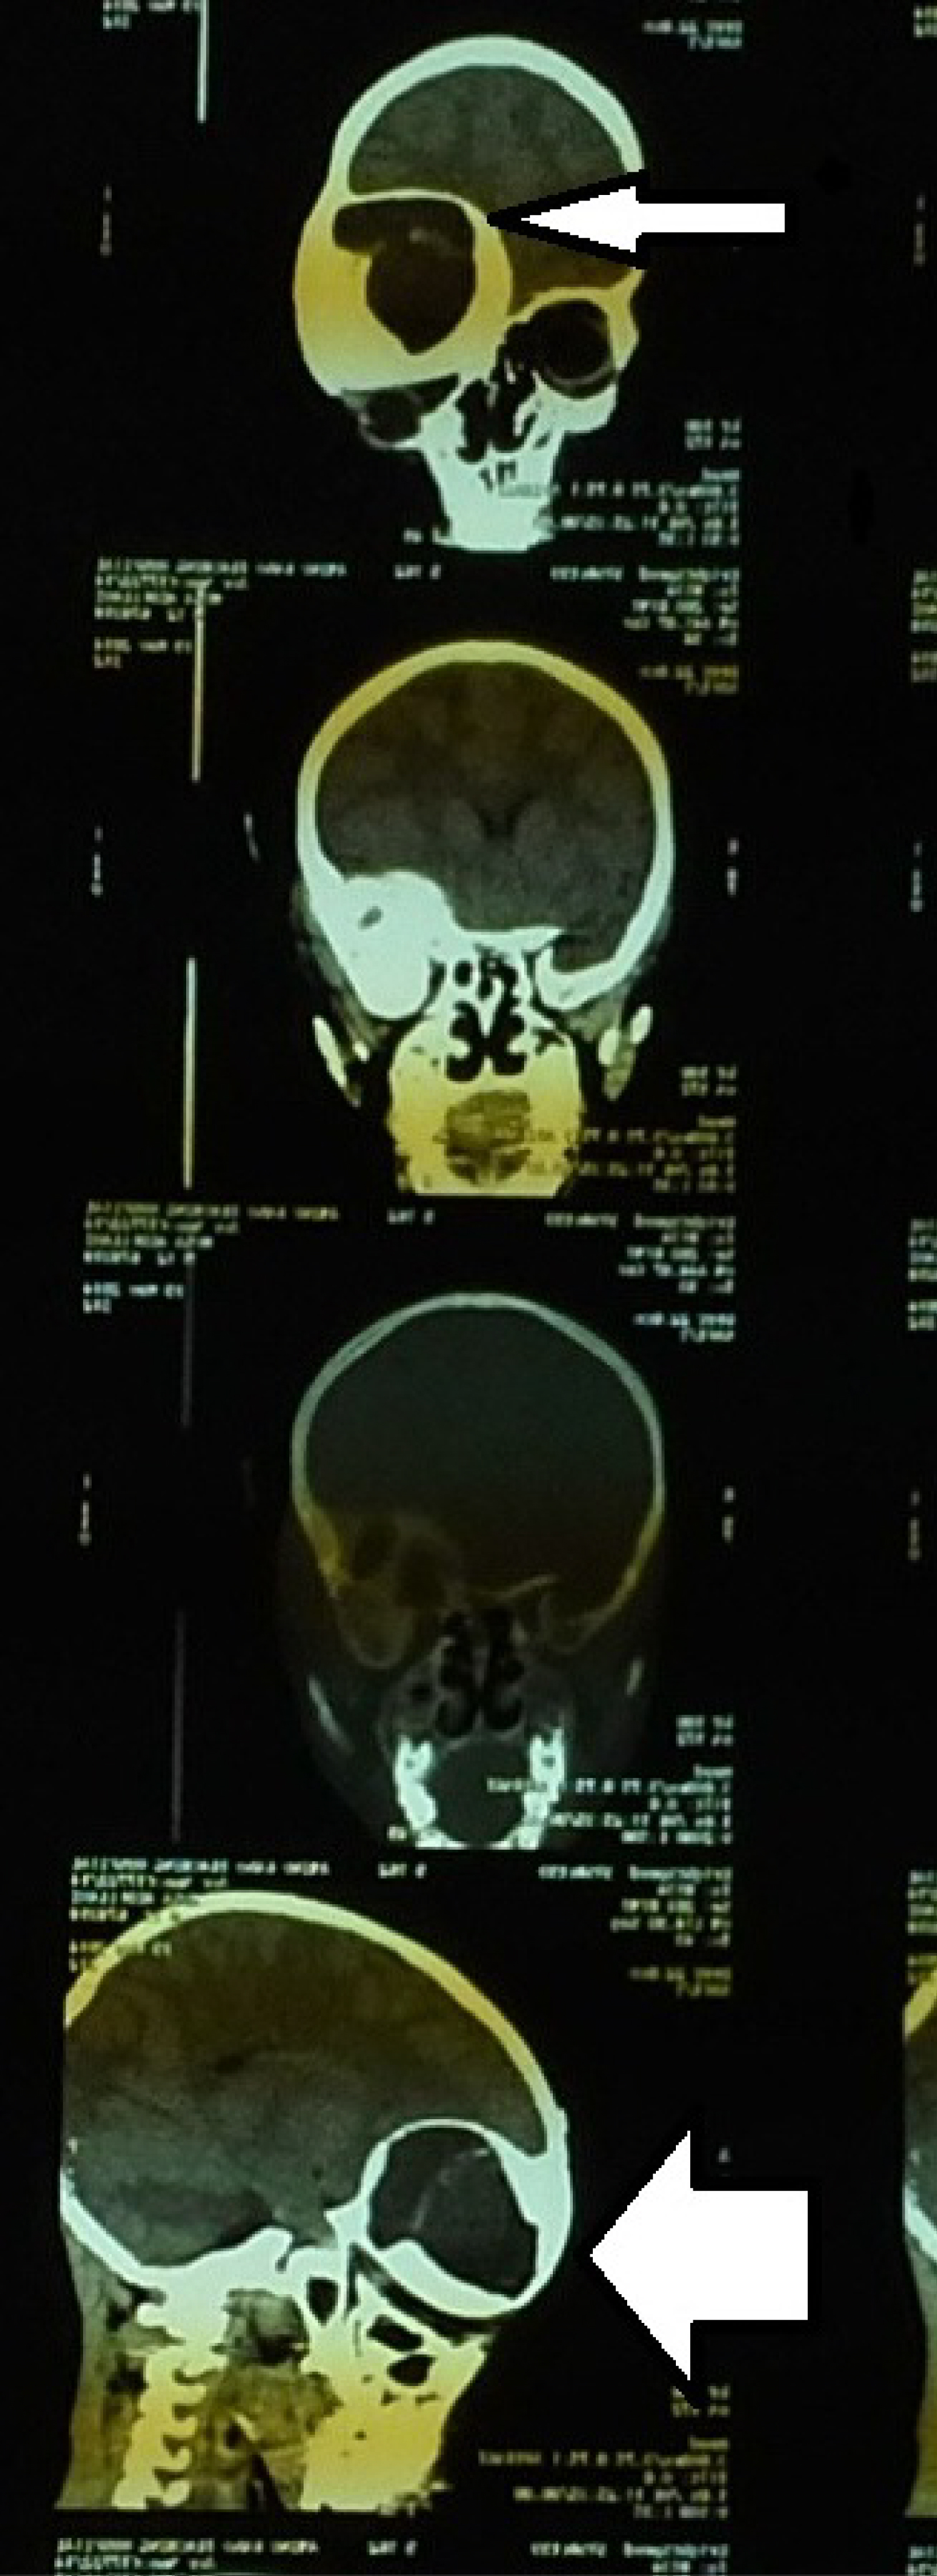

The primary reasons for seeking treatment in all patients were craniofacial swelling and aesthetic disturbance [10]. Though, reports from previous studies were in tandem with our findings other remarkable clinical features were visual impairment, pain and pathological fractures which were absent in all our cases [1,4,11]. Monostotic fibrous dysplasia has been reported to occur four times more often that polyostotic type however, polyostotic fibrous dysplasia affects craniofacial regions in 90% of the cases [2,6,12]. This conforms to the findings of our study of polyostotic fibrous dysplasia in all the cases (Figure 4A and Figure 4B).

Figure 4A: Axial cut CT scan showing left fronto-orbital fibrous dysplasia. View Figure 4A

Figure 4B: Coronal and sagittal views CT scan of a patient with fronto-orbital fibrous dysplasia. View Figure 4B

Computerised tomography (CT) scan is an invaluable imaging modality for the assessment of craniofacial fibrous dysplasia because of its ability to delineate bony structures accurately [1,9]. The characteristic CT scan appearance of fibrous dysplasia consists of: ground glass pattern (56%), homogenously dense pattern (23%) and cystic appearance (21%) [1]. Magnetic resonance imaging provides more detailed soft tissue resolutions than CT scan but, it is not recommended because low signal from bone affected by fibrous dysplasia could be misdiagnosed for neoplasms [1,9].